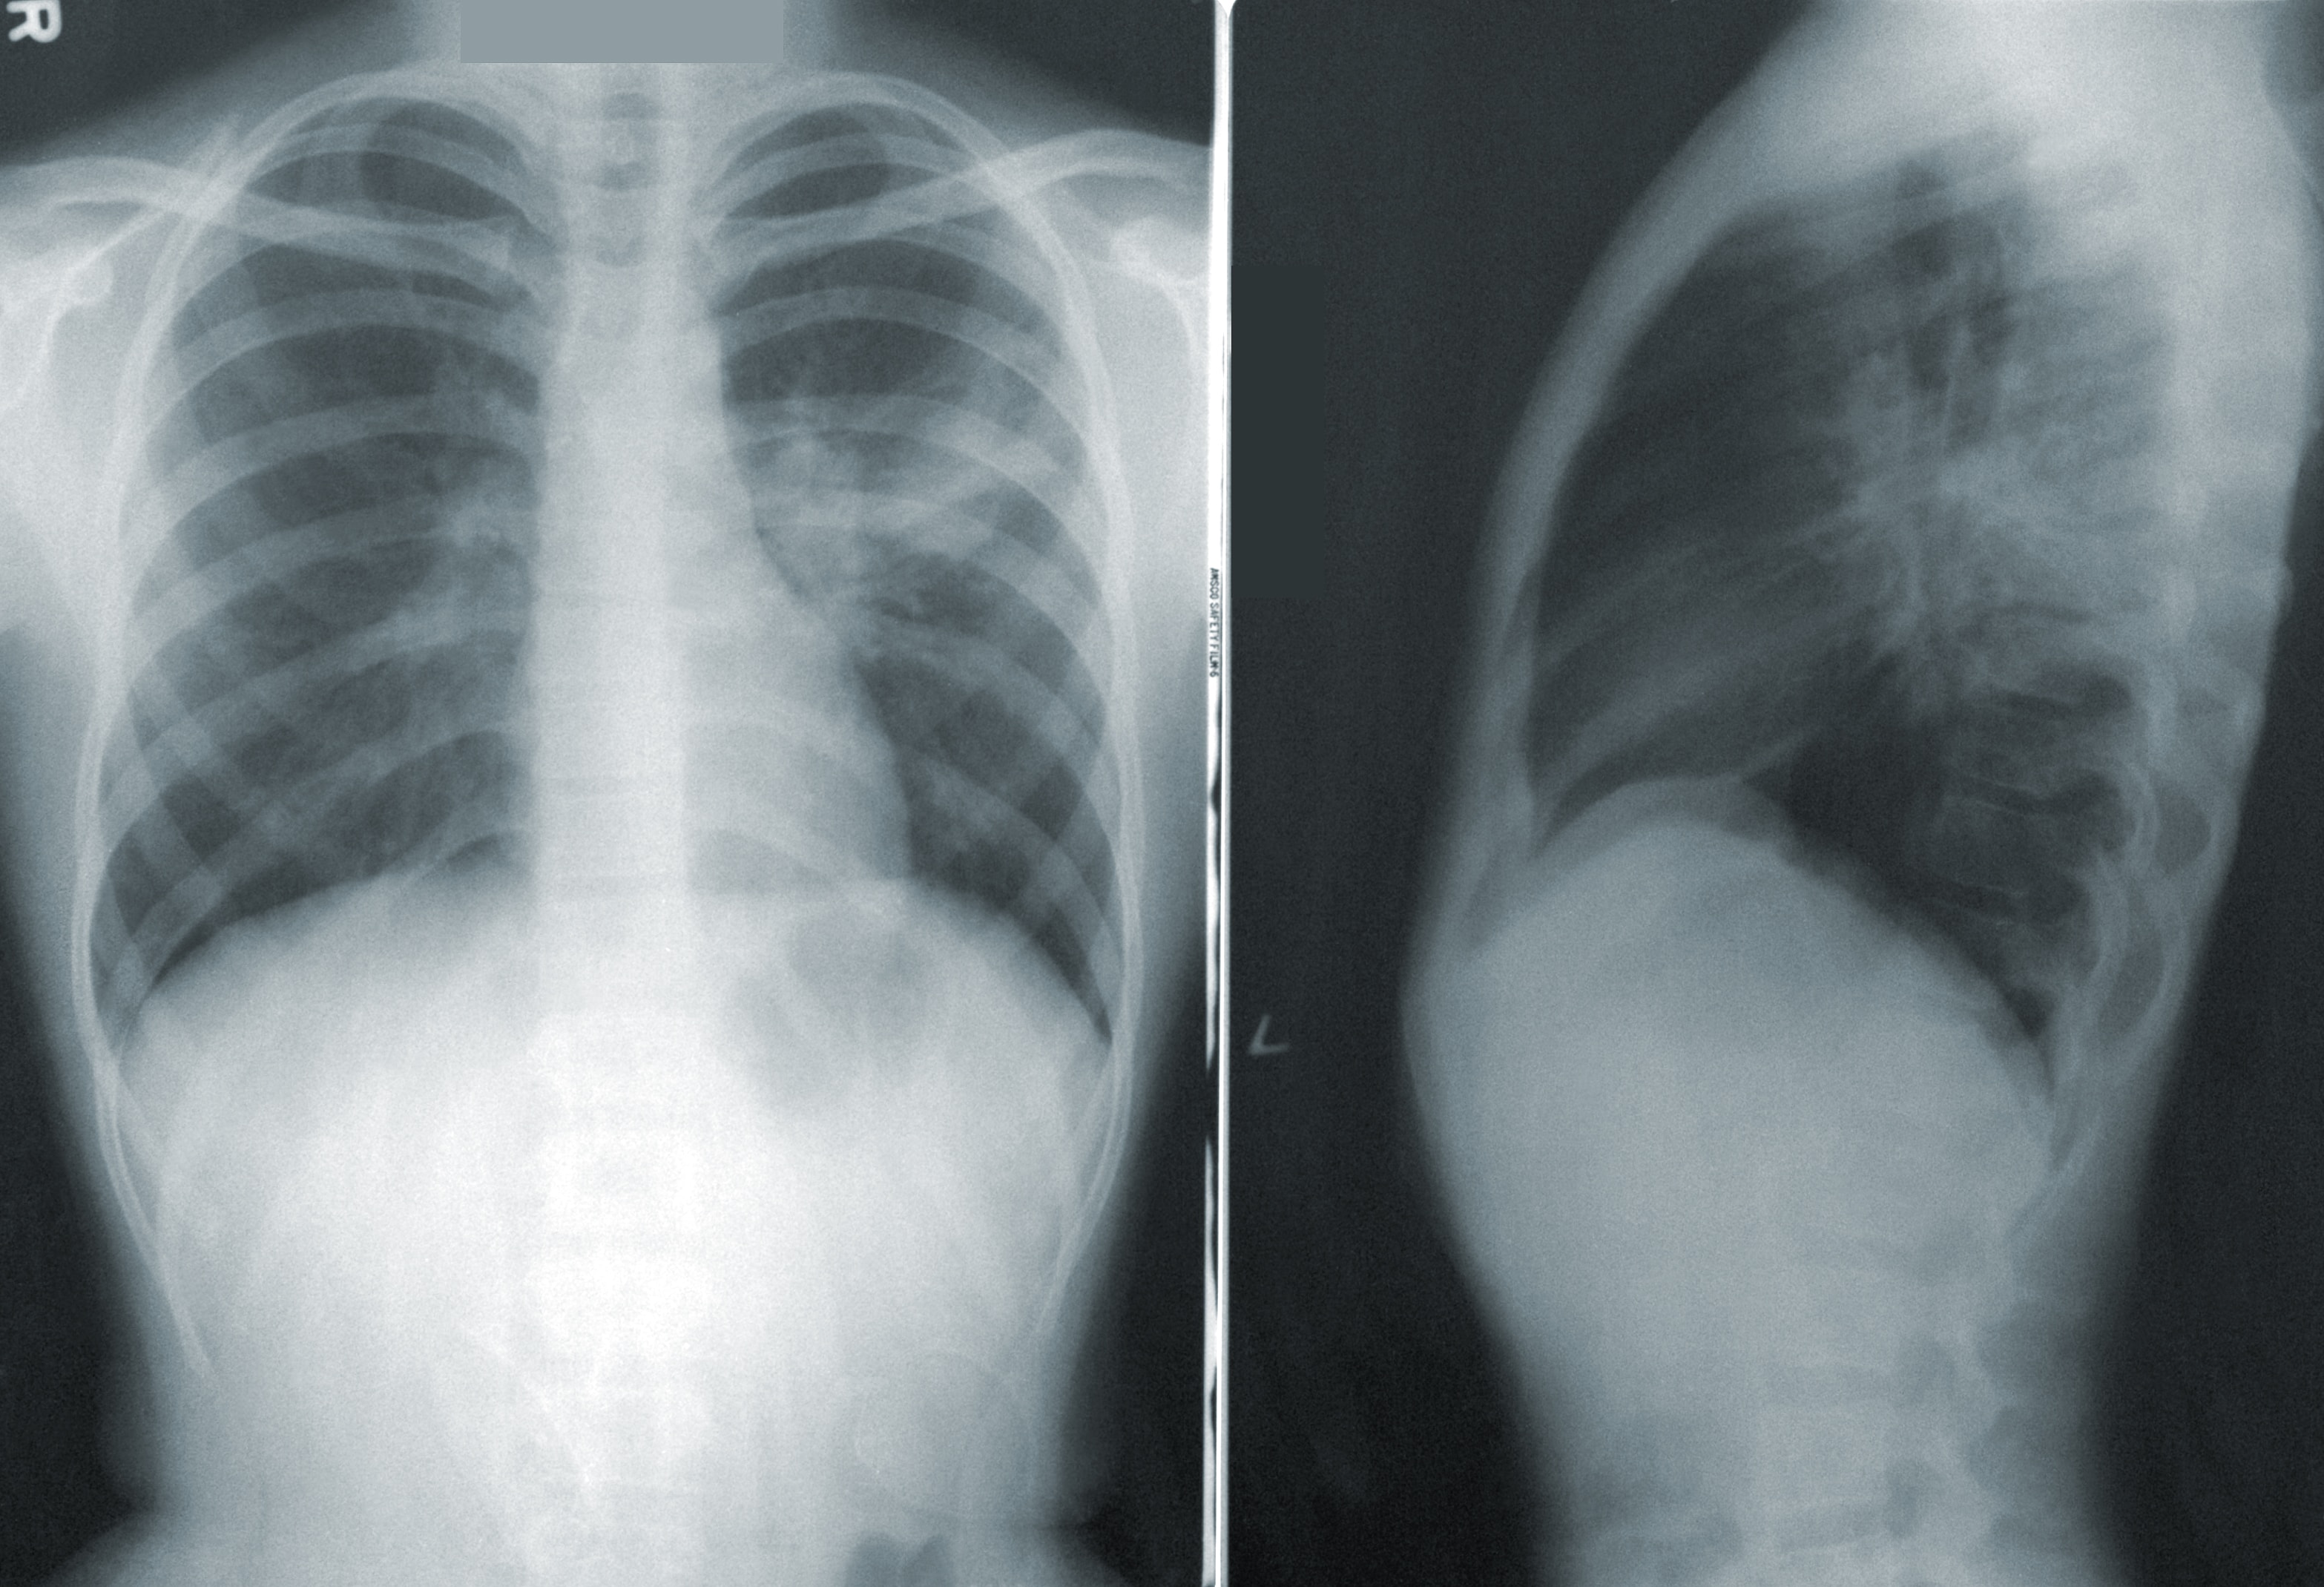

폐렴의 진단

의료진은 폐렴을 진단하기 위해 환자의 증상을 평가하고, 청진기로 폐의 소리를 들어보며 X-레이 또는 CT 스캔을 통해 폐의 상태를 확인합니다. 가끔은 증상이 애매한 경우에는 혈액 검사나 기침 샘플을 통해 원인을 확인하기도 합니다.